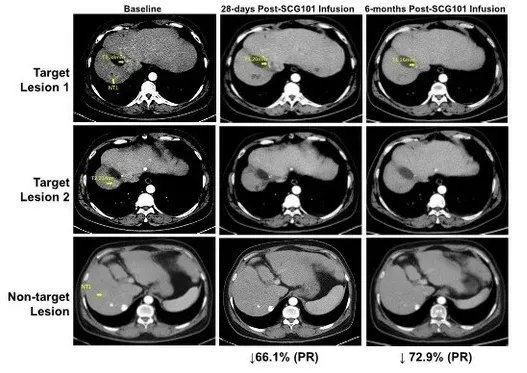

具体来看,该患者接受单剂SCG101输注后,第28天靶病灶较基线缩小66%,达成部分缓解(PR);治疗第4个月,肿瘤进一步缩小至74.5%,另一处病灶完全消失(详见下图)。值得关注的是,试验期间患者未接受其他任何抗肿瘤治疗,截至数据统计时,肿瘤无进展时间已超6.9个月,持续维持缓解状态。

▲图源“SCG”,版权归原作者所有,如无意中侵犯了知识产权,请联系我们删除

此外,回输前后的肝脏免疫组化分析显示,乙肝表面抗原阳性肝细胞实现100%清除;HBV血清学标志HBsAg水平也显著下降,从输注前的557.96IU/mL降至输注后第7天的1.3IU/mL,第28天进一步降至0.08IU/mL(详见下图)。